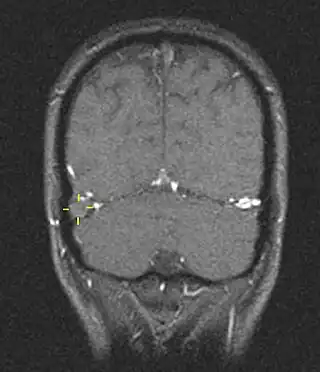

![]() Trombosis del seno venoso cerebral vista mediante resonancia magnética | ||

La trombosis del seno venoso cerebral (CVST) es la presencia de trombosis (coágulo sanguíneo) en el seno venoso dural, que recibe sangre de venas externas e internas del cerebro. Los síntomas de esta enfermedad pueden incluir dolor de cabeza, visión anormal, cualquiera de los síntomas de un accidente cerebrovascular (debilitamiento de los músculos de la cara y extremidades de una mitad del cuerpo) e infartos. El diagnóstico se realiza normalmente por tomografía axial computarizada (CT/CAT scan) o resonancia magnética (MRI) empleando el contraste radiológico para demostrar obstrucción de los senos venosos por trombos.[1]

Hay varias formas de neuroescaneo que pueden determinar la presencia de la trombosis del seno venoso cerebral. Los edemas cerebrales e infartos venosos pueden hacerse visibles en cualquier modalidad, pero para la detección del trombo sí, el tipo de escaneo más usado comúnmente son la tomografía axial computarizada (CT) y la resonancia magnética (MRI). Ambas usan varios medios de radiocontraste para elaborar un venograma y visualizar las venas en torno al cerebro.[1]

La tomografía axial computarizada tiene una capacidad de detección que para algunos expertos supera la de la resonancia magnética. Esta prueba se basa en la inserción, a través de una inyección en la vena (normalmente en el brazo), de una sustancia radiopaca. Tras un tiempo, el que tarda el torrente sanguíneo en llevar la sustancia al cerebro, el escaneo se realiza. La sensibilidad de este test es de 75-100% (detecta de 75 a 100% de todos los coágulos presentes), y una especificidad de 81-100% (sería incorrectamente positivo en un 0-19%).[6]

La resonancia magnética venosa emplea los mismos principios, pero la modalidad de escaneo usada es la resonancia magnética. La MRI tiene la ventaja de ser mejor a la hora de detectar peligro para el cerebro como resultado del incremento de la presión en las venas obstruidas. No obstante, este mecanismo no se encuentra disponible en muchos hospitales y su interpretación puede resultar dificultosa.[6]